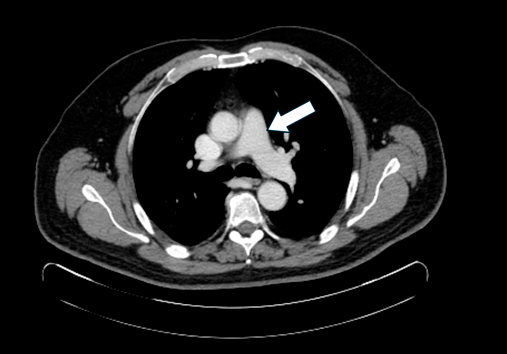

Tumor Miofibroblástico Inflamatorio. Caso clínico y estado del arte.

Cristian Roa-Cáceres, Miguel Roa-Cáceres